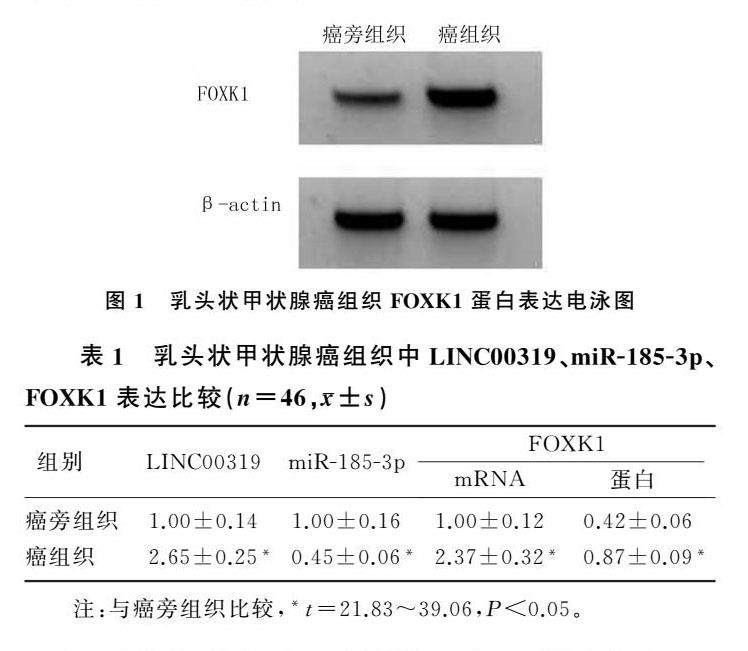

论著 | LINC00319通过miR1853p/FOXK1轴对乳头状甲状腺癌细胞的作用

论著 | LINC00319通过miR1853p/FOXK1轴对乳头状甲状腺癌细胞的作用